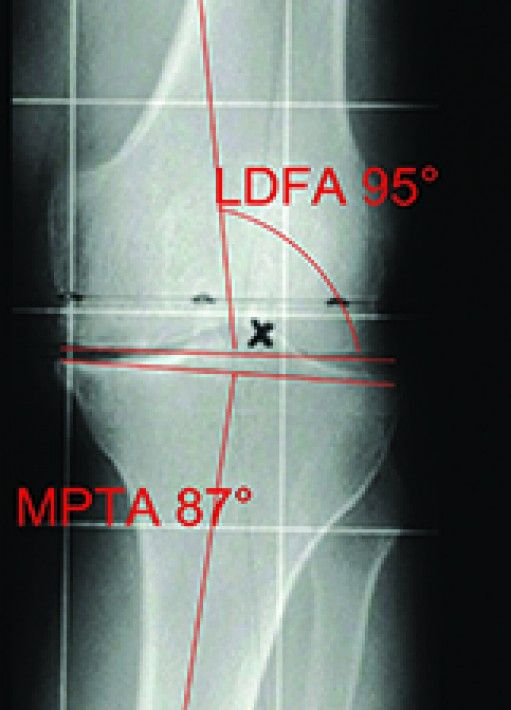

MO TV Gérard Deschamps - Lateral femorotibial arthritis (LFTA) associated with genu valgum: ethiopathogeny and surgical consequences , Maîtrise Orthopédique janvier 2016